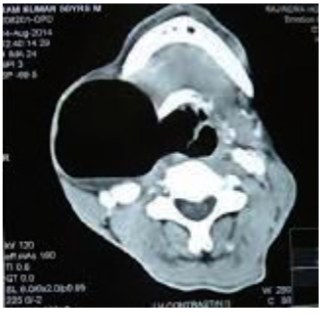

Parapharyngeal Abscess

- Question: 25 years old male came with history of tonsillitis 2 weeks ago managed with Abx, developed 3 days history of SOB + odynophagia.

- Answer:

- Diagnosis?

- Parapharyngeal abscess

- Whatโs the treatment?

- External drainage (to avoid injury of internal structure), I.V antibiotics, Airway Management